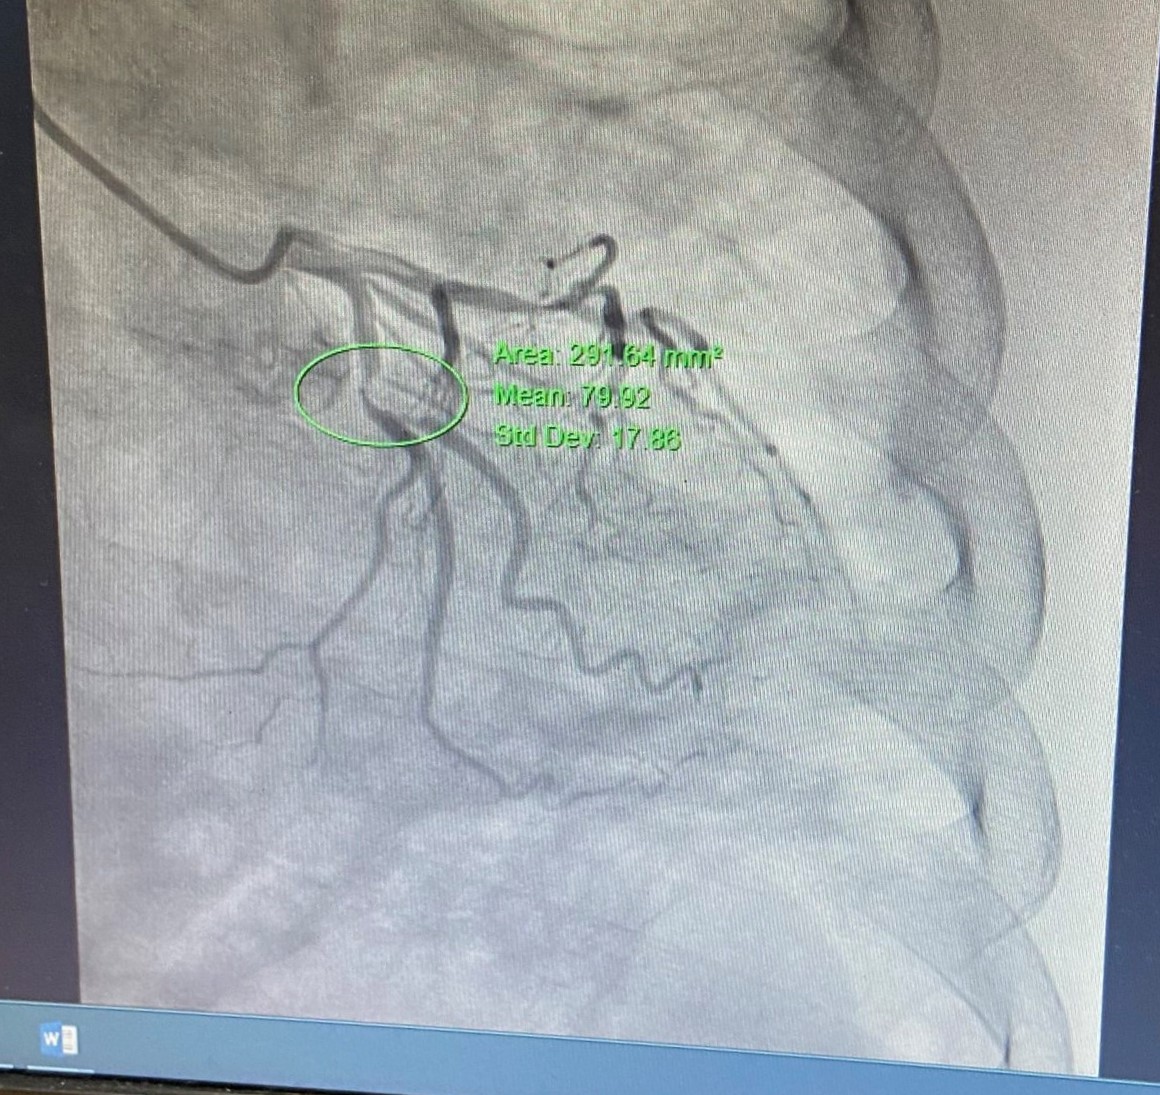

Trường hợp thứ 2 trên bệnh nhân nam 80 tuổi, nửa tháng nay xuất hiện cơn đau thắt ngực không ổn định, tăng khi gắng sức, kéo dài 5-10 phút, khó thở trong cơn. Bệnh nhân có tiền sử COPD, giãn phế quản, tăng huyết áp, tiểu đường. Thực hiện chụp mạch vành qua da phát hiện bệnh nhân có tổn thương rất nặng, hẹp rất khít 2 thân động mạch vành; hẹp 99% liên thất trước (LAD) I-II, xơ vữa gây hẹp 99% động mạch mũ (LCx) I-II. Nếu không can thiệp kịp thời, bệnh nhân dễ dẫn đến nhồi máu cơ tim cấp và các biến chứng nguy hiểm. Bệnh nhân nhanh chóng được xử trí can thiệp, đặt 1 stent mạch vành tại vị trí LCx I-II. Sau can thiệp, bệnh nhân giảm cơn đau thắt ngực, nhánh thứ 2 sẽ can thiệp tiếp khi đã ổn định.